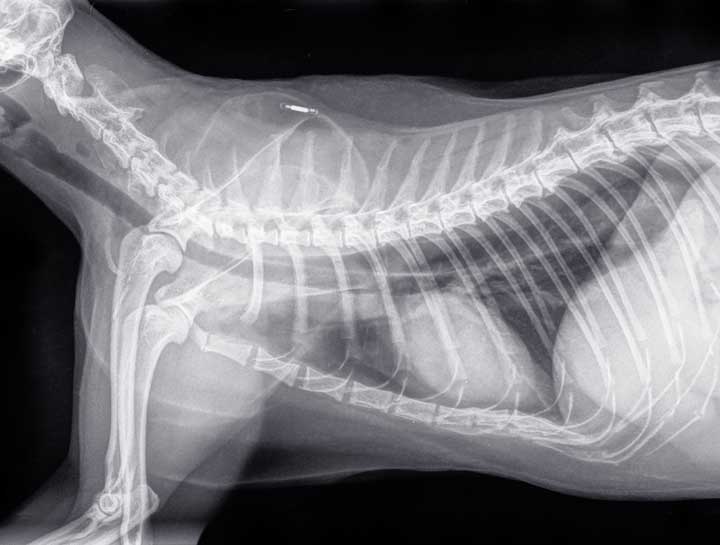

A microchip is an electronic device that’s only about the size of a grain of rice. It gets implanted between the shoulder blades and remains there indefinitely, although it is possible for a microchip to migrate. The implant procedure is relatively painless and it’s as quick and easy as receiving a shot.